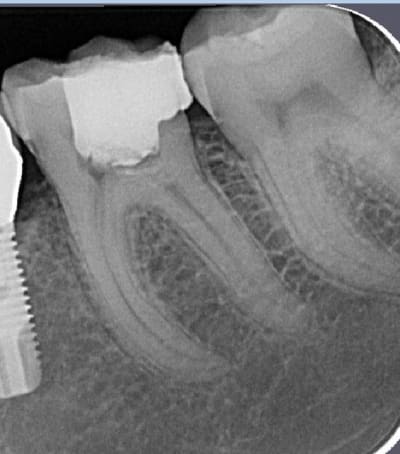

T'as pas autre chose, une photo sans le pansement, une radio, une photo des autres dents ?

Mais il y a fort à parier au regard de la courbure importante de la racine mésiale qu'il faudra élargir cette chambre en mésiale, à ceci s'ajoute une carie débutante toujours en mésiale (sans parler des caries multiples un peu partout), donc on se dirige à mon avis vers de la prothèse périphérique.

la limite distale finira en juxta osseux.non?

effectivement implant 35 suite à la perte de la 75 tardivement ( agénésie de la 35 )